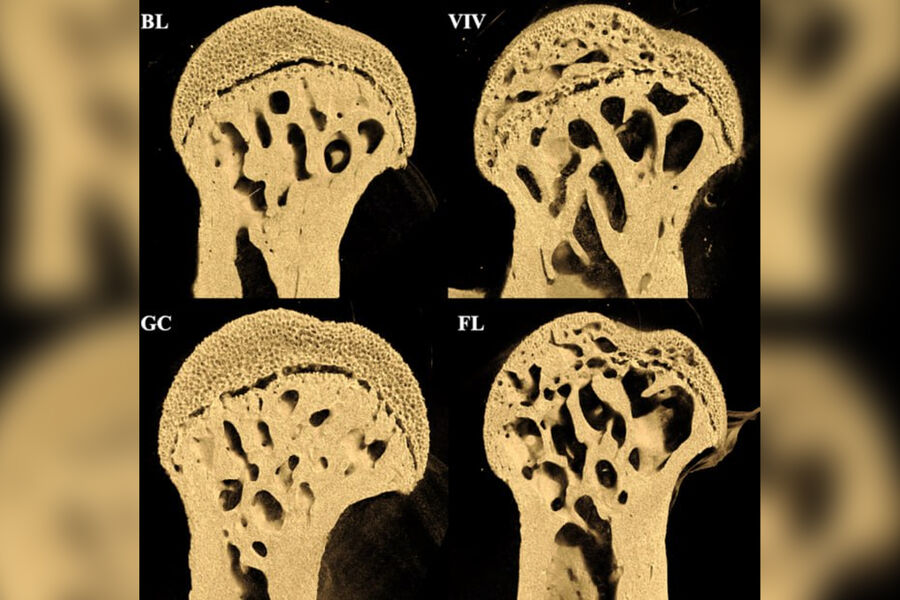

PLOS One: в невесомости у мышей образуются отверстия на концах бедренных костей

Эксперимент продолжительностью 37 дней показал, что у мышей в космосе значительно пострадали бедренные кости, в то время как поясничный отдел позвоночника остался практически неповрежденным.

Особенно заметные повреждения — крупные отверстия — обнаружились на концах бедренных костей в местах соединения с тазобедренным и коленным суставами.